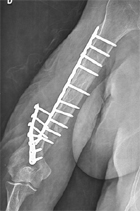

Mme P., 68 ans, vient vous consulter car elle ne peut plus relever sa main droite qui reste pendante.

A l’examen, vous diagnostiquez une paralysie des extenseurs de la main correspondant à une atteinte du nerf radial au bras.

Vous regardez le bras et vous êtes alerté par une importante angulation postérieure du bras.

A l’interrogatoire, Mme P. a fait une première chute, 1 an auparavant avec fracture de l’humérus ostéosynthésée, puis une nouvelle chute 2 mois après avec une nouvelle fracture plus bas située sur l’humérus,